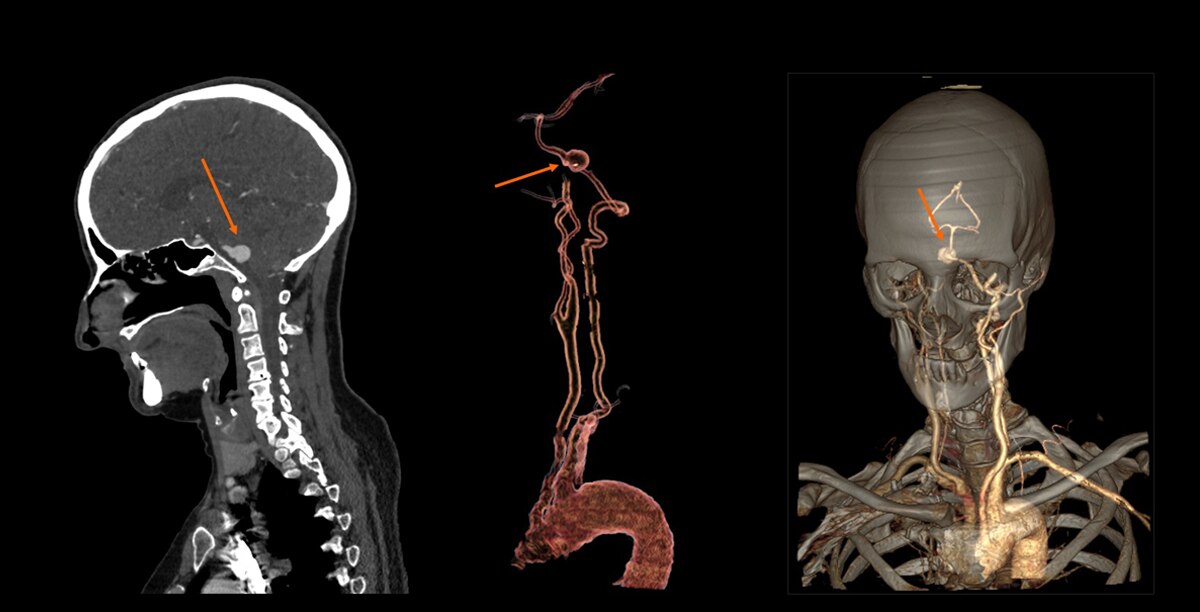

Carotids, assessment of aneurism at 1.8 mSv1

Circle of Willis